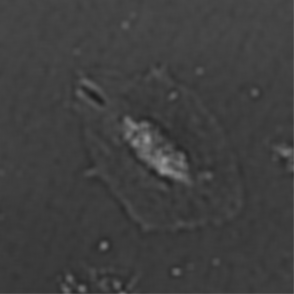

(b) Frame 2. Beginning of cell spreading

Figure 3: Original images of sequence is example of high dynamics of cell behavior affecting on contrast properties

The Fig.3 is representing couple of frames of sample image sequence with relatively high contrast between foreground and can be segmented with almost 95% accuracy with any method we used. Frame 1 of sample sequence presented at Fig.3(a) contain regions of hyper contrast pixels. In this case such condition does not affect on valid recognition since they are belong to object and present on margins of it and differs well from background. For Frame 2 there is absence of such pixels (Fig.3(b)) and this conditions also makes segmentation possible in relatively inflexible filtering conditions. The Frame 2 has relatively low contrast however it is seen that after filtration applied on image we achieve good difference of core and cell body compared to background as it presented at Fig.4 .